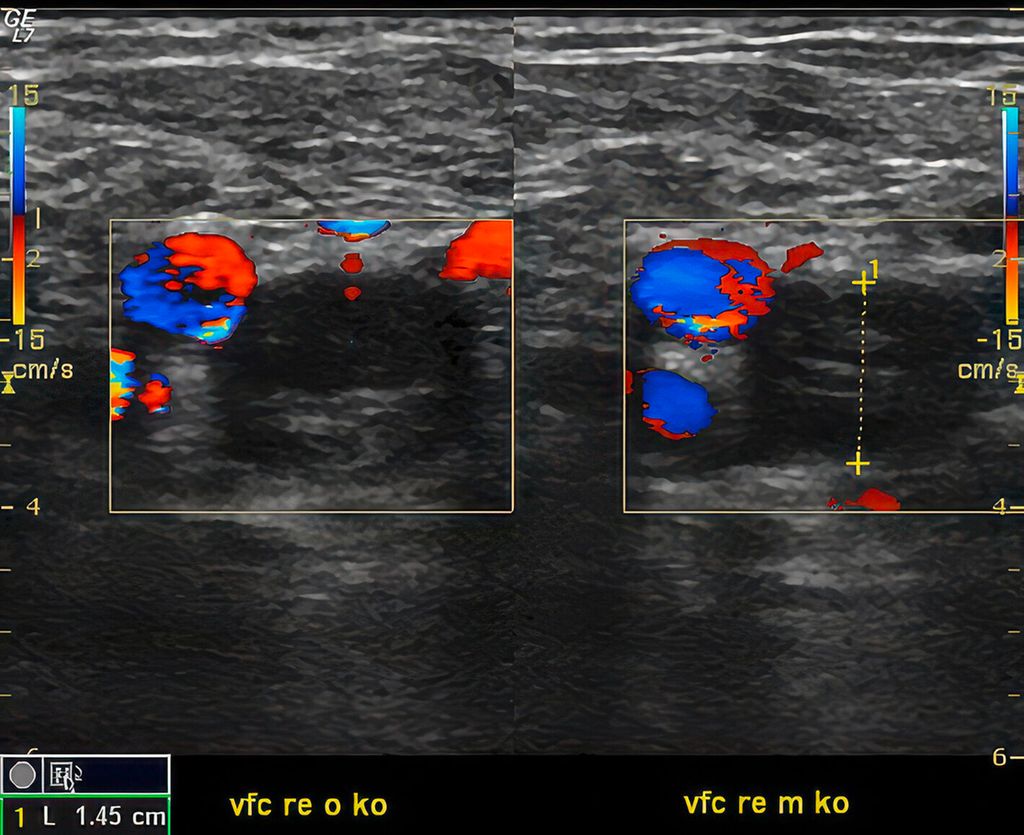

Die tiefe Beinvenenthrombose äußert sich am häufigsten mit einer einseitigen Schwellung am Unterschenkel bei distalen Thrombosen oder am ganzen Bein bei proximalen Thrombosen. Beim akuten Verschluss der Beckenvenen kann es zu einem massiven Ödem mit livider Verfärbung der Haut, gefüllten oberflächlichen Hautvenen und einer Marmorierung der Haut mit Livedo reticularis oder Livedo racemosa kommen (Abb.1a). Die Diagnose erfolgt mittels Duplexsonografie (Abb. 1b), die Klinik ist nicht pathognomonisch. Zum Unterschied dazu wird bei der oberflächlichen Venenthrombose die Diagnose klinisch gestellt. In diesem Fall sind alle Zeichen einer Entzündung vorhanden: rubor, color, tumor, dolor, functio laesa.

Es ist zu betonen, dass die gründliche Anamnese und körperliche Untersuchung die wichtigsten ersten Schritte in der Diagnosestellung sind und in manchen Fällen alleine ausreichen. Als wichtigste diagnostische apparative Untersuchung hat sich die Duplexsonografie bewährt. Mithilfe dieser nichtinvasiven, fast überall verfügbaren, schonenden und günstigen Methode können sowohl vaskuläre als auch nichtvaskuläre Ursachen visualisiert und mithilfe der klinischen Untersuchung und Laborbefunde die richtige Diagnose gestellt werden. In speziellen Fällen mit abdomineller oder pelviner Beteiligung können weiterführende Untersuchungen wie MRT oder Computertomografie (CT) ergänzend notwendig sein.

Zusammengefasst können verschiedene Ätiologien zu Beinödemen führen. Die Duplexsonografie ist die wichtigste apparative Untersuchung, um eine exakte Diagnose stellen zu können. Generell gilt, dass bei einseitigen Schwellungen venöse oder lymphatische Ursachen am wahrscheinlichsten sind. Bei bilateralen Ödemen sollen systemische Ursachen oder Medikamente als Erstes angedacht werden. Oft können gleichzeitig mehrere Faktoren eine Rolle spielen. Wichtig im klinischen Alltag ist, potenziell gefährliche Fälle zu identifizieren und zu behandeln, um lebensbedrohliche Komplikationen zu verhindern.